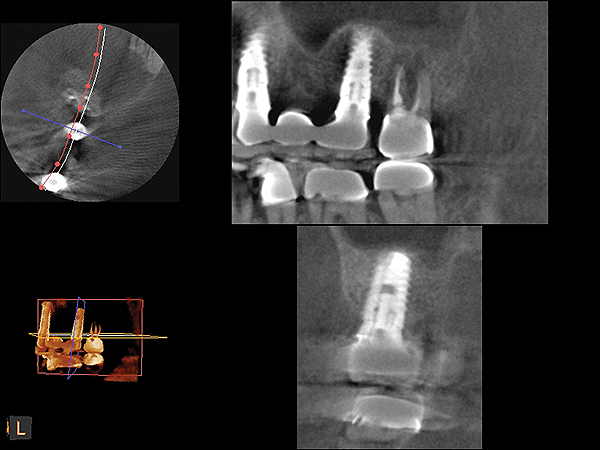

Because the bone grafting materials used in this technique need physical stability during healing to support the raised membrane, there is a high probability that significant shrinkage of the graft will occur as it heals and matures if only non-demineralized material is used. For these reasons, a composite graft using calcium sulfate, DFDBA, and mineralized particulate bone is used. A 50:50 mixture by volume of mineralized bone grafting material and DFDBA is used, to which approximately 40% calcium sulfate by volume is added. A higher percentage of calcium sulfate is used relative to that described for composite grafting in other uses, because some of the calcium sulfate will wash out during bone packing. Another advantage to this composite graft is that it is not as radiopaque as a purely mineralized graft. This allows radiographic monitoring of the bone healing around the implant, which can be used to time abutment placement on the implant. This is demonstrated in Figure 4 and Figure 5, which are radiographs taken on the day of the initial surgery showing the radiographic appearance of the composite graft, implant, and graft, and in Figure 6, a 5-month postoperative radiograph with the abutment in place. The old floor of the sinus is indistinguishable from the area of new bone. Figure 7 shows a CBCT scan (Carestream Dental, www.carestreamdental.com) taken at 4 months with the old floor of the sinus indistinguishable from the new bone formed.

Fig 7. 4-month CBCT scan (Kodak 9000D) of implant No. 14.

Figure 7

Fig 19. CBCT scan (Kodak 9000D) of implant No. 14 showing homogeneous appearance of the bone.

Figure 19

Fig 22. CBCT scan (Kodak 9000D) of No. 3 area, day of placement. Appearance of native bone and bone graft is clearly discernible.

Figure 22